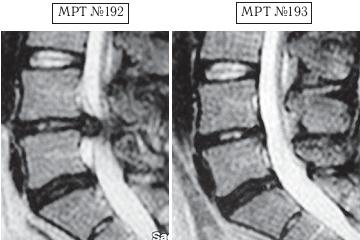

Напомню, что в большом спорте есть большая проблема — это допинги. Допинг в переводе с английского слова «doping» (от dope) означает «давать наркотики». По сути, это в основном химические препараты (фармакологические и другие средства), способствующие стимуляции физической и нервной деятельности на непродолжительное время. Иногда ими пытаются искусственно усилить физическую активность и выносливость спортсмена на время спортивных соревнований. В зависимости от специфики спортивной деятельности в качестве допинга могут использоваться, например, симпатомиметические амины (эфедрин, амфетамин, метиламфетамин и т. д.), стимуляторы центральной нервной системы и восстанавливающие, укрепляющие аналептики (трансамин, стрихнин, лептамин и т. д.), общестимулирующие средства (препараты лимонника китайского, женьшеня, левзеи и т. д.), этиловый алкоголь, наркотики, болеутоляющие средства (морфин, его производные, опиум) и другие препараты. Многие специалисты, не понаслышке знакомые с проблемами большого спорта, отмечают, что современный большой спорт — это уже не старый добрый спорт, где люди показывали свои физические достижения, а это уже во многом соревнование биохимиков по созданию лучшего допинга. Хотя с данной проблемой постоянно борется на международном уровне Всемирное антидопинговое агентство (ВАДА) — независимая организация, созданная при поддержке Международного олимпийского комитета (МОК), каждый год ужесточая антидопинговый контроль, однако всё равно каждый год фарминдустрия выдаёт новые «сюрпризы»-препараты. Печально то, что все эти химические допинги, которые тайно принимает спортсмен для одномоментного улучшения результата, неизменно отражаются на его здоровье, нанося ему ущерб. Ведь весь этот процесс носит экспериментальный характер, а это значит, что последствия для организма вполне могут стать необратимыми, а в некоторых случаях дело может закончиться и летальным исходом, что неоднократно случалось в практике большого спорта. Однако мало кто из спортсменов задумывается в момент приёма допинга о его отдалённых последствиях для своего организма. Многие спортсмены находятся в плену ошибочных стереотипов, которые гласят, что «если не будешь принимать допинг, не сможешь победить». Однако не зря говорится: «Познай себя и ты познаешь весь мир». Возможности человеческого организма многократно превышают возможности искусственной химии. Свидетельством тому является множество известных науке случаев, связанных как со спортом, так и с жизненными обстоятельствами, когда человек в экстремальных, чрезвычайных ситуациях способен проявить такие феноменальные способности и возможности, которые не всякий чемпион сможет повторить. Человеческий мозг — это далеко не изученная, сложная система центрального управления организмом, которая может функционировать в разных режимах, о чём неоднократно упоминается, например, в работах академика Натальи Петровны Бехтеревой. Так что не стоит искать обманчивых путей для достижения высот, ведь ничто не проходит в этой жизни бесследно. Как писал Омар Хайям: «Нищим дервишем ставши — достигнешь высот. Сердце в кровь разорвавши — достигнешь высот. Прочь, пустые мечты о великих свершеньях! Лишь с собой совладавши — достигнешь высот». Так что в любом деле важна внутренняя составляющая человека. Ради справедливости должен заметить, что среди моих пациентов, помимо спортсменов, немало просто самодисциплинированных людей, которые в полной мере ответственно, целеустремлённо подходят к вопросам своего здоровья. Это радует, поскольку понимаешь, что твой труд не пропадёт даром. Ведь если пациент столь тщательно будет следить и беречь своё здоровье и дальше, то организм ещё долго послужит ему верной службой. А это в свою очередь означает, что в жизни данного человека станет намного меньше проблем и он получит полноценную возможность для самореализации. Как говорится в пословице: «Жизнь дана на добрые дела». А тем читателям, кто на сегодняшний день обременён проблемой заболевания позвоночника, хочу сказать, что не стоит отчаиваться. Люди справлялись ещё и с худшими ситуациями. Доказательством тому служат как вышеизложенные, так и нижеприведённые случаи, которые даже высокопрофессиональным специалистам когда-то казались безнадёжными. Думаю, комментарии здесь излишни. Пример № 1. ![]() На МРТ № 192 наблюдается состояние поясничного отдела позвоночника: рецидив после операции — секвестрированная грыжа межпозвонкового диска в сегменте LIV-LV, абсолютный стеноз спинномозгового канала. На МРТ № 193 — состояние поясничного отдела позвоночника после лечения методом вертеброревитологии. Пример № 2. ![]() На МРТ № 194 наблюдается состояние поясничного отдела позвоночника после трёх операций: рецидив — грыжа межпозвонкового диска в сегменте LV-SI стеноз спинномозгового канала. На МРТ № 195 — состояние поясничного отдела позвоночника после лечения методом вертеброревитологии. Пример № 3. ![]() На МРТ № 196 наблюдается состояние поясничного отдела позвоночника после операций: рецидив грыжи межпозвонкового диска в сегменте LV—SI с формированием секвестра с миграцией в краниальном направлении, абсолютный стеноз спинномозгового канала. На МРТ №s197 — состояние поясничного отдела позвоночника после лечения методом вертеброревитологии. Пример № 4.